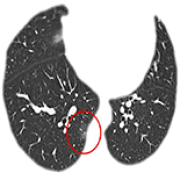

14 Nov 2021 : Clinical Research

Clinical Features and Temporal Lung Radiographic Changes in 25 Patients Recovering from COVID-19 Pneumonia: A Retrospective Case-Control Study

Chao Hu, Jian Ping Zeng, Ke Peng, Hong Xia, Huan Ming Zhang, Zhi Zhong, Ming Yan Jiang

3,640 973 0